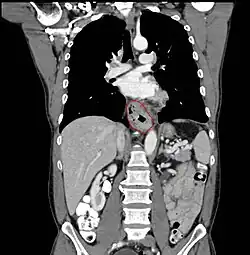

Anatomy

- AJCC divisions of the esophagus: (These are based on adjacent surgical landmarks)

- Upper thoracic esophagus:

- Thoracic inlet to lower border of the azygos vein

- Middle thoracic esophagus:

- Lower border of the azygos vein to the inferior pulmonary veins

- Lower thoracic esophagus and EG junction:

- Inferior pulmonary veins to the stomach; includes the intraabdominal portion of the esophagus

- By endoscopy, 30 to 40 cm

- Resectability often limited:

- Lack of fibrous serosa to prevent local spread

- Rich lymphatic network in submucosa and muscularis that allows longitudinal and circumferential drainage